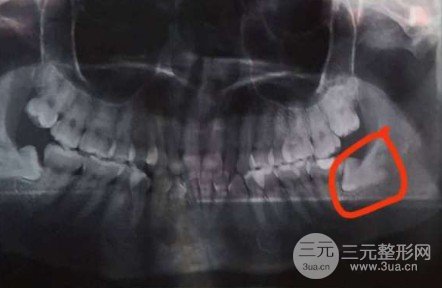

在口腔醫(yī)院開始拔除頭一個(gè),位置就在左下,長得很奇怪吧。在醫(yī)院掛的一般的號(hào),醫(yī)生就很和善,一面拔一面跟我說話,跟我說這是在干嘛做什么,不需要害怕。打上mz就著手拔了,拔智齒的流程一點(diǎn)都不疼,主要是內(nèi)心害怕,30分鐘吧就拔好了。之后幫我醫(yī)用冰袋,跟我說常見問題,掛完水就回去了。

mz之后都不疼,拔完第二天疼了一整天之后就沒事了,覺著痛感能夠承受,幫我開的止痛藥我也沒吃,漸漸地的傷口就在痊愈。不過左下阻生拔完的多久后,我感覺自己阻生周圍的那顆槽牙松動(dòng),心里害怕的很,不過嫌麻煩也沒有去附屬口腔醫(yī)院。漸漸地的那顆大牙穩(wěn)定了不晃動(dòng)了。不過在后面的6個(gè)月內(nèi),忽然發(fā)覺那個(gè)大牙愈來愈歪,如今已經(jīng)咬不著了。那顆大牙原本就深齲了,所以也許拔掉智齒對(duì)它也有一點(diǎn)影響。